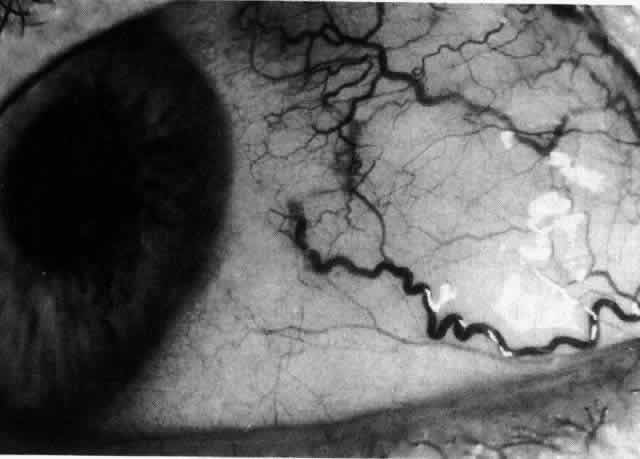

Fig. 28. Nodular scleritis. Both the anterior conjunctival slit and the deep scleral

slit are displaced forward by the scleral edema. There is little

separation between these two beams, indicating that all the edema is in

the sclera and not in the overlying episclera. (Watson PG, Hayreh S, Awdry P: Episcleritis and scleritis. Br J Ophthalmol 52:278–279, 1968) Fig. 28. Nodular scleritis. Both the anterior conjunctival slit and the deep scleral

slit are displaced forward by the scleral edema. There is little

separation between these two beams, indicating that all the edema is in

the sclera and not in the overlying episclera. (Watson PG, Hayreh S, Awdry P: Episcleritis and scleritis. Br J Ophthalmol 52:278–279, 1968)

|